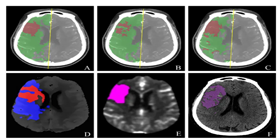

医疗诊断

已应用于西医医疗设备医疗诊断和中医诊断,为诊疗提供辅助决策支持。